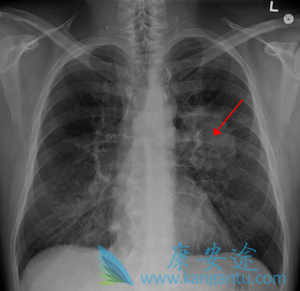

肺癌中晚期能活多久与肺癌治疗方法有很大关系

肺癌中晚期能活多久 ,没有一个特定的日期,但是只要选对方法,就一定能争取肺癌的生存期方面取得一定的成效。      最近,不时有报道称,哪个明星又得 肺癌 死了,在所有的肿瘤疾病中,肺癌的发生最常见,不过很多肺癌患者最关心的莫过于自己能活 ...